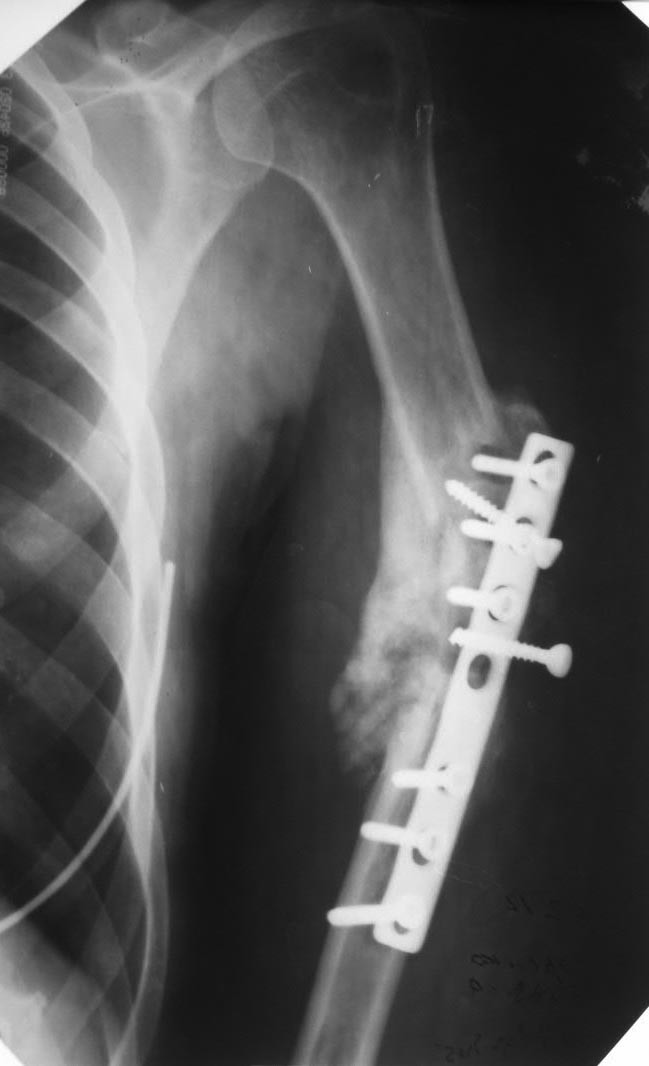

дефект-диастаз левой плечевой кости

Два года назад - перелом плеча.

Последовательно ставили три пластины. На все - отторжение металла.

Сейчас - дефект-диастаз+укорочение. Суммарный дефект около 6 см. Дырки от винтов. Инфекции нет.

В данном случае отсутствуют симптомы металлоза, потому что не видны обьективные данные, такие, как наличие боли, образование локальных некротических участков, формация кист и псевдотуморов. Но явно видны следы неудачной фиксации и слабой хирургической техники.